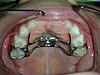

1.Appareils orthopédiques (disjoncteurs, PUL, activateurs, masque de Delaire…)

3.PUL: appareil orthopédique pour phase d'interception: appareil "magique" qui permet le déplacement des mâchoires